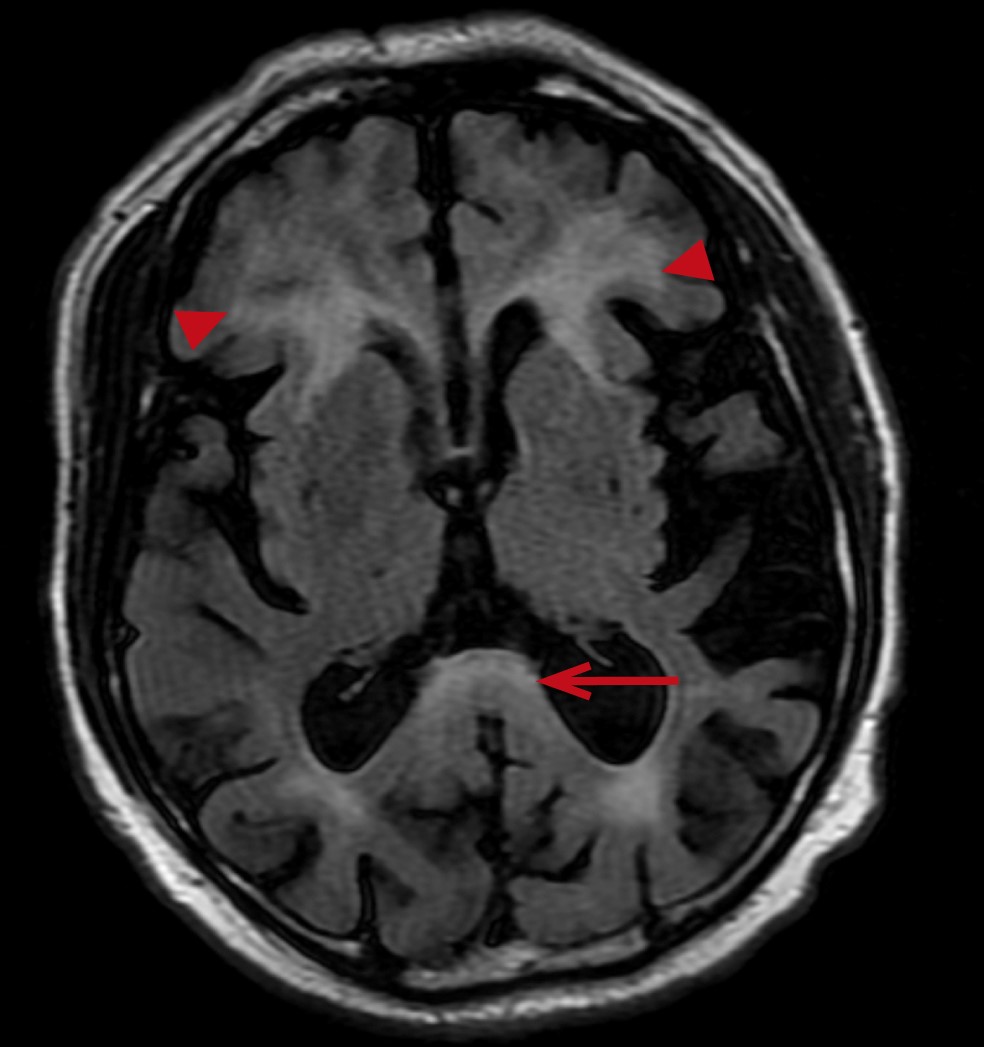

Brain MRI (05.02.2025): the observations include a diffuse inhomogeneous increase of the MRI-signal from white matter of the brain for Т2- and Т2-FLAIR (Fluid-Attenuated Inversion Recovery) images with spreading to the middle cerebellar peduncles and the cerebellum hemispheres, with linear-stellar increase of the MRI-signal for the DWI mode, with no signs of diffusion restriction. Conclusion: “MRI signs corresponding to the manifestations of the neurodegenerative diseases (FXTAS). Diffuse cerebral atrophy grade I” (Fig. 2, 3).

Fig. 2. Symmetrical foci of high signal in the T2-weighted images at the level of the middle cerebellar peduncles.

Fig. 3. Hyperintensity in the area of the splenium of corpus callosum in a series of FLAIR (long arrow), additional finding — foci of symmetrical periventricular leukoaraiosis near the anterior horns (short arrows).